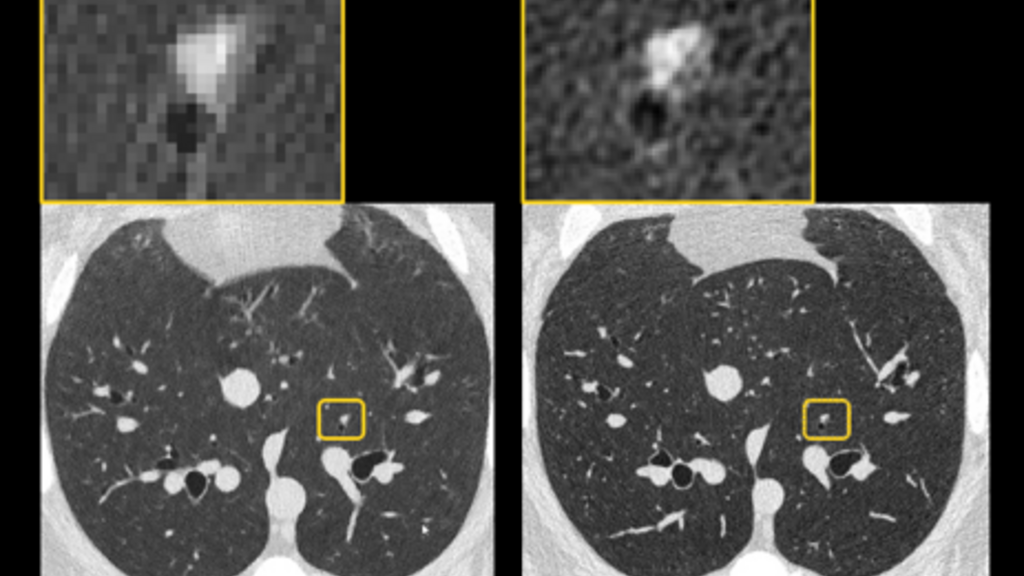

Radiomic Assessment Image

Chest CT Protocols for Radiomic Assessment

Our group has worked on the optimization of CT imaging protocols and/or validation of quantitative CT biomarkers for the assessment of lung structure.